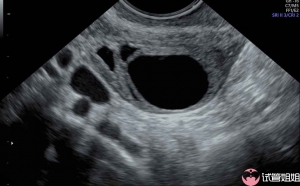

子宫情况